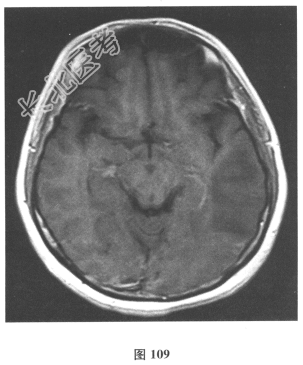

- 简答题2、脑脊液检查:常规、生化均正常,CSF-病毒TORCH(-),抗Hu、Yo、Ri均阴性,OB、MBP正常。血清抗Hu、Yo、Ri均阴性。颅脑MRI显示左颞枕、右顶枕多发长T₁、长T₂信号,Flair高信号,病变累及皮质及皮质下白质,病灶无强化,见图108~图114。根据颅脑MRI,需要鉴别的疾病应是